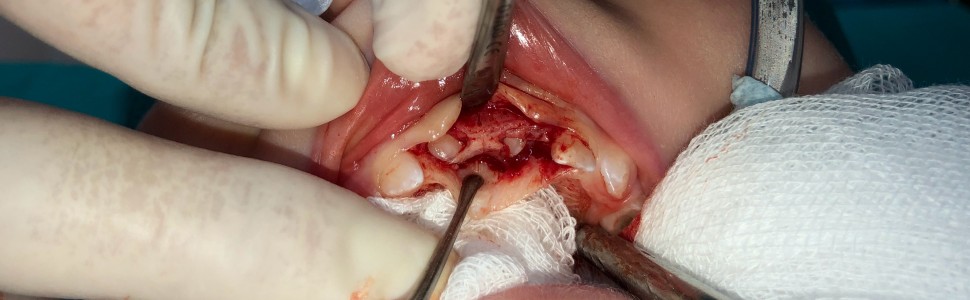

Chirurgiczne leczenie intruzji zębów mlecznych. Opis przypadku

Surgical treatment of intrusive luxation in the primary dentition – case report

Urazy zębów mlecznych stanowią częsty powód zgłaszania się dzieci do gabinetów stomatologicznych. Jednymi z najpoważniejszych urazów zębów są intruzje. Leczenie wtłoczonych zębów mlecznych polega najczęściej na wnikliwej obserwacji klinicznej i radiologicznej ponownego ich wyrzynania. Istnieje szereg wskazań do usunięcia intrudowanych zębów mlecznych.

Dental injuries in the primary dentition are common reason for children’s and their parents visits in the dental offices. Intrusive luxations are one of the most serious traumatic dental injuries. The most common treatment procedure in intrusive luxation in the primary dentition is their careful clinical and radiological observation. There are indications for intruded primary teeth extraction.